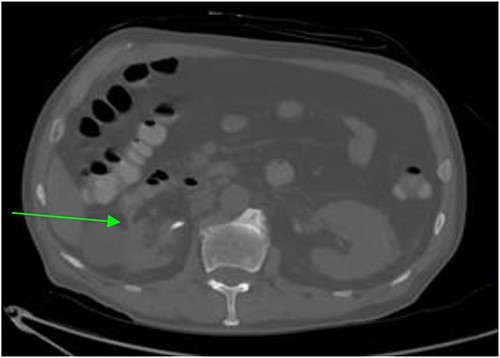

Repeat abdominal CT revealed a fistulous connection between the 3rd portion of the duodenum and the right proximal ureter with oral contrast pooling inferiorly in the mid-distal right ureter (Fig. 1). Nephrostogram confirmed a frank fistulous connection between the proximal ureter and duodenum. Additionally, a second fistula originating from the collecting system superiorly was suspected due to contrast extravasation tracking directly to the 2nd portion of the duodenum (Fig. 2).

CT abdomen and pelvis revealing a right sided renal-duodenal fistulous connection.